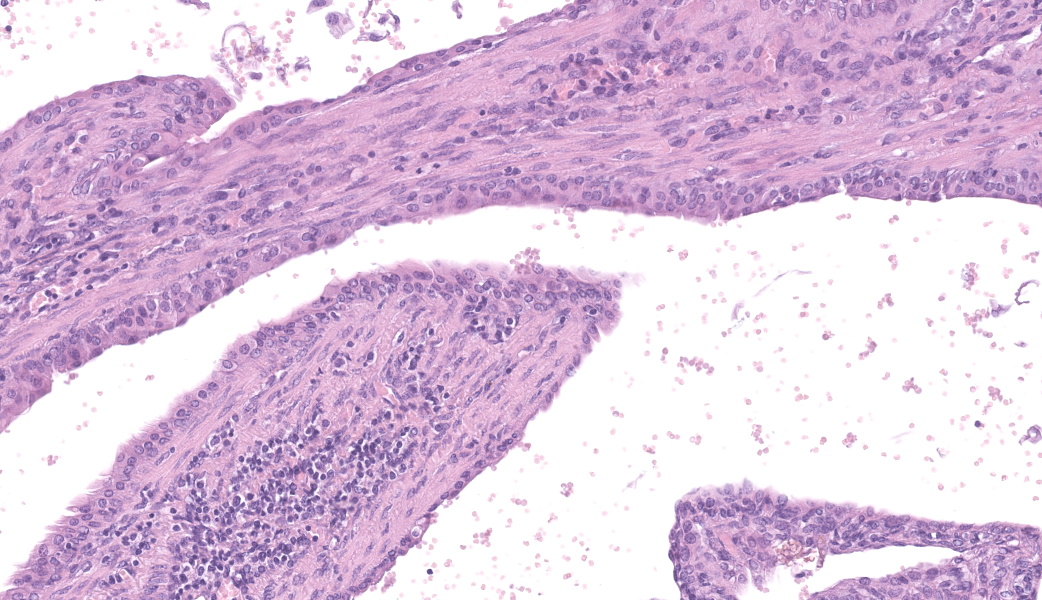

Left kidney: The left kidney is composed of multiple, largely dilated cavities that divide the kidney into numerous islands of parenchyma. These cavities are lined by 2–4 layers of cuboidal to highly columnar, eosinophilic epithelial cells with no mitotic activity (collecting ducts). Few sloughed epithelial cells and erythrocytes are present in the lumen of these ducts. The parenchyma contains islands of immature glomeruli with peripheral nuclei, poorly developed capillaries, and thickened Bowman’s capsule (vimentin positive). Primitive tubules are lined by large basophilic cuboidal epithelial cells with minimal or absent lumina. Other areas within the parenchyma consist of mature tubules and glomeruli with some tubules showing mild dilation and intraluminal protein casts. Collecting duct-like structures are multifocally surrounded by loosely arranged mesenchymal tissue (primitive mesenchyme). The interstitium is multifocally expanded by fibrous connective tissue and some areas are infiltrated by low to intermediate numbers of lymphocytes, plasma cells, macrophages, and occasional neutrophils. Some arteries are very prominent (large) with thickened media, and they appear tortuous. A medium sized artery is surrounded and infiltrated by inflammatory cells predominantely macrophages, neutrophils and occasionally multinucleated giant cells within adventitia, media and intima (transmural). Diffuse proliferation of fibroblasts and deposition of fibrin within the vessel wall is observed. Occasionally, the tunica intima is disrupted. Endothelial cell proliferation is evident with clustering of endothelial cells attempting to recanalize the affected lumina.

The large number of fetal glomeruli, presence of few primitive tubules, and occasional primitive mesenchyme, especially in a 5-week old mouse, certainly suggest a degree of renal dysplasia. Mouse kidneys should be completely developed within 4 days of birth (no later than 7 days).1,5 However, there was debate amongst conference attendees on whether this was a primary renal dysplasia or a secondary delay in maturation due to atrophy caused by congenital hydronephrosis/hydroureter. The fetal glomeruli were strikingly obvious in this case and are characterized by a reduction in the number of capillaries, the presence of podocyte nuclei that palisade around the periphery of a small glomerular tuft, decreased tuft segmentation, and a thick Bowman’s capsule. Immature glomeruli are, in a not-so-convoluted kidney, usually best seen in the subcapsular cortex.1,5 Glomeruli aside, however, while there were rare definitively primitive tubules, most participants thought that many of the tubules were atrophied in response to the severe hydronephrosis rather than truly dysplastic. This was further complicated by the complete lack of medullary distal convoluted tubules. Additionally, there were occasional glomeruli that were mature and the majority of the scant interstitium was relatively developed. As such, many conference participants preferred the term “asynchronous maturation” to describe the spectrum of development seen within the kidney.

Participants wholeheartedly agreed with the contributor regarding the arteritis and similarly diagnosed polyarteritis nodosa (PAN) due to the degree of subintimal proliferation, neutrophilic inflammation, disruption of the elastic laminae, fibrinoid necrosis, and tortuosity of the arteries. Although usually associated with hypertension and most commonly seen in the pancreas, mesentery, and testes, renal PAN is well-documented.2,4 In this case, it is possible that the degree of hydronephrosis and subsequent pressure atrophy could have contributed to the development of hypertension-like lesions in the arteries, although this is purely speculative and could be a separate process entirely.

The flocculent, cystic spaces made definitive interpretation of this case challenging. The lining of the cystic spaces resembled either persistent metanephric ducts (ducts in the outer medulla lined by pseudostratified, ciliated, columnar epithelium), transitional urothelium, and/or serosa. Metanephric ducts in the medulla potentially represented persistent, incompletely differentiated ureteric bud branches that did not differentiate into normal collecting tubes as they are supposed to, further suggesting a congenital etiology in this condition.5,10 The presence of serosa-lined spaces implies that some cysts had collapsed in on themselves during processing. Everyone unanimously agreed, however, that this was not polycystic kidney disease.